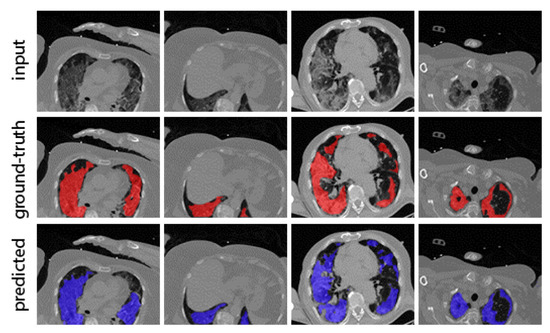

5.2.1. Lesion Segmentation Results

| mDice (%) | mIoU (%) | |

|---|---|---|

| Lesion Seg. | 97.8 (+1.1–7.9%) | 95.6 (+1.5–8.7%) |